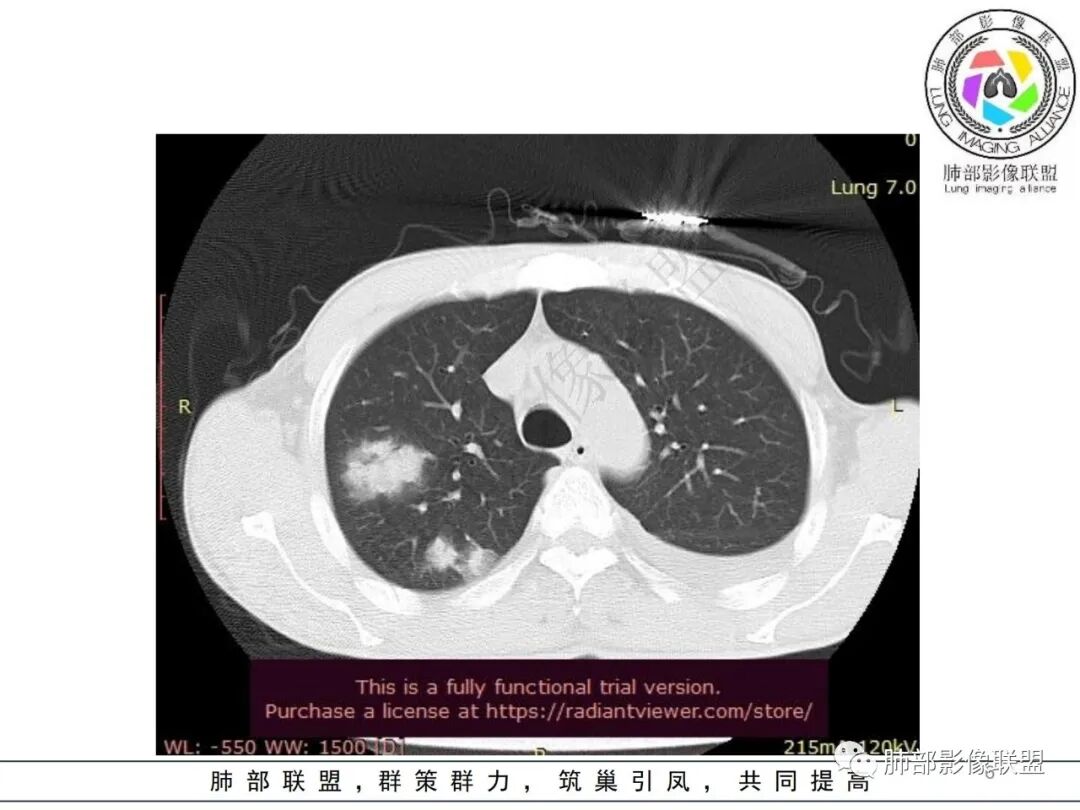

双肺多发大小不等结节影,边缘伴有磨玻璃影,边界欠清,部分与血管束相连,支气管似有穿行病灶内,结节有融合,左肺下叶厚壁空洞,伴有反晕征,左侧胸水,临床中年男性,发热40℃,CRP增高,感染性病变,1:类鼻疽伯克霍尔德菌(好发海南,影像表现也符合)

影像:双肺多发结节、实变影,大部分病灶边界不清,分布相对随机,左下肺坏死空洞形成,伴左侧胸水。

影像表现:双肺弥漫分布斑片影、实变影、磨玻璃影、结节影,晕征、反晕征,随机分布,部分病灶空洞形成前兆,左侧胸腔积液。

两肺多发斑片状实变影,周围GGO

主体还是沿支气管,大片叶段性分布

影像上急性感染,大叶性病变为主

单凭影像:鹦鹉热、军团要考虑,因为内部无坏死,非典型气道为主

影像表现:双肺多发结节、实变影,大部分病灶边界不清,随机分布趋势,左下肺“反晕征”,似有形成空洞趋势。左侧胸腔积液。治疗后复查 ,大部分病灶吸收好转,呈较为典型血播分布,肝脏低密度块影,边界不清,符合肝脓肿。